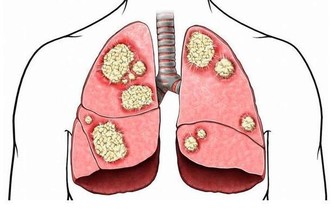

2 遠離白內障:一年200多萬例白內障手術,你還不注意補充葉黃素?

白內障是晶狀體上不透明或半透明的區域,白內障是世界範圍內導致失明的主要眼疾。

僅在1994年在美國就做了200萬例白內障消除手術。

最近的研究發現:通過增加葉黃素的攝入量和降低白內障發生率在統計學上呈顯著性的趨勢。

在BDE(Beaver Dim Eye Study)長達五年的縱向追踪調查中也發現,

葉黃素攝人量高組比攝人量低組白內障發病的發病率顯著降低。